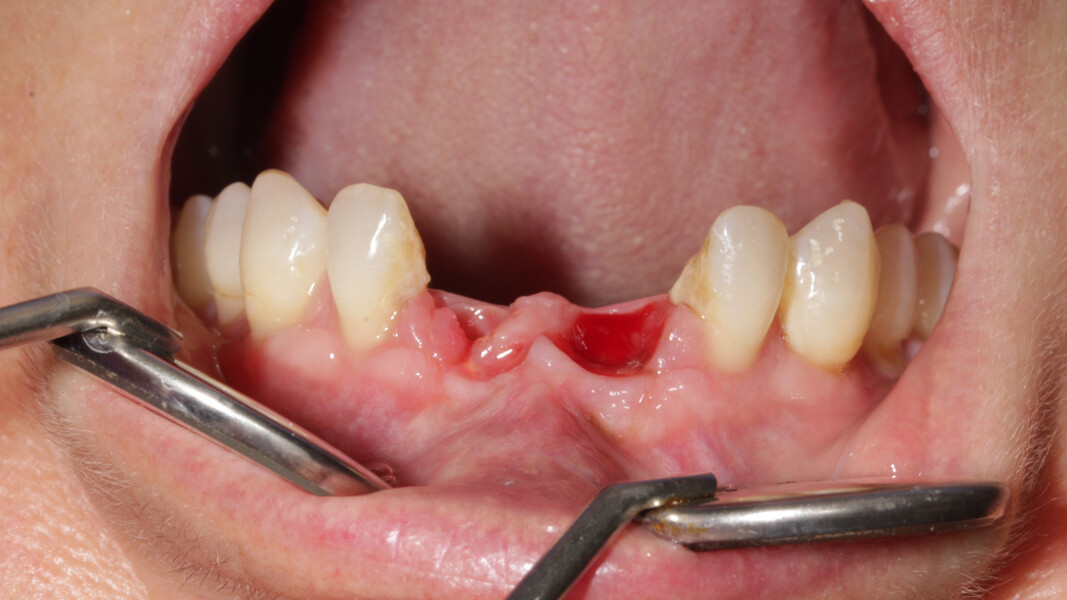

Le but du traitement est le remplacement des quatre incisives par un bridge implanto-porté de 12 à 22. Le plan de traitement mis en place est le suivant : extraction des deux incisives centrales et réalisation d’un bridge provisoire dento-porté fixe de 12 à 22 ; trois mois de temporisation permettant la cicatrisation des tissus mous, ainsi que la mise en oeuvre de la thérapeutique parodontale (Fig. 27) ; extraction de 12, 22 et 18, mise en place des implants, reconstruction de la crête (avec les racines extraites), mise en place d’un bridge provisoire fixe de 12 à 22, transvissé sur les deux implants.

Nous réalisons un lambeau avec une incision crestale décalée en palatin en 11 et 21, sulculaire en 12, 13, 22, 23, en prenant soin de préserver les papilles interdentaires, ainsi que deux décharges verticales en distal des canines. Nous réalisons un décollement de pleine épaisseur (Figs. 28 et 29). Les dents (12, 22 et 18) sont facilement extraites et les alvéoles curetées avec soins. Deux implants (4*13) sont positionnés dans la paroi palatine des alvéoles, il subsiste une déhiscence vestibulaire en 22. Les racines de 12, 22 et 18 sont séparées dans le sens de la longueur. Les racines préparées comme indiqué ci-dessus, sont vissées en vestibulaire et en occlusal de la crête, au moyen de vis d’ostéosynthèse (diamètre 0,9 mm), afin de reconstruire la crête osseuse au niveau des inters de bridge ainsi que la paroi vestibulaire de la crête au niveau de 22 (Figs. 30 et 31). Le gap vestibulaire entre les implants et la crête ainsi que l’espace entre la crête et le greffon au niveau de 21, sont comblés avec un matériau d’origine synthétique (Collapat II Symatese). Le lambeau est tracté, suturé coronairement avec un fil tressé synthétique 5.0 (Fig. 32). Des piliers coniques droits pour prothèse plurale transvissée sont posés, et une empreinte prise à la fin de l’intervention (Fig. 33). Un provisoire est réalisé dans la journée par notre laboratoire de prothèse et posé le soir même. (Figs. 34 et 35)

Les sutures sont retirées à 15 jours. Un contrôle de la bonne ostéointégration des implants est réalisé à 2 mois postopératoire (Figs. 36 et 37). La réalisation de la prothèse d’usage par notre correspondant intervient à 9 mois postopératoire (Fig. 38).